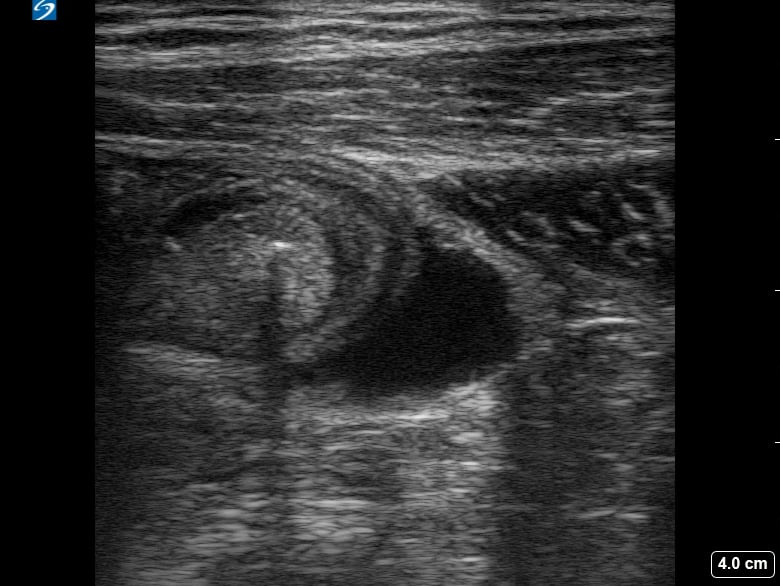

An ovarian cyst is a fluid-filled sac that develops on or within an ovary. Common in OBGYN, most ovarian cysts are benign and resolve spontaneously, but some may cause symptoms like pelvic pain or pressure, or indicate underlying conditions like polycystic ovary syndrome (PCOS). Ultrasound is the primary imaging modality for detecting and characterizing these cysts, providing crucial details on their size, shape, and internal features.

Accurate ultrasound assessment is vital for differentiating simple cysts from more complex or suspicious masses, guiding appropriate medical management and follow-up in gynecological practice. Early detection and precise characterization through medical ultrasound enhance diagnostic accuracy and optimize patient care.